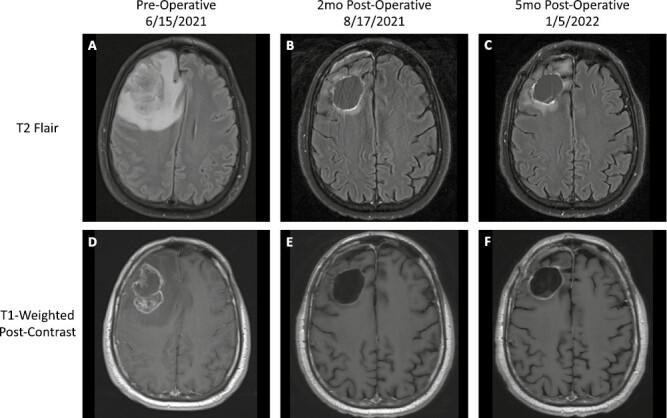

Homologous recombination repair (HRR) pathway deficiency opens multiple therapeutic avenues within pancreatic cancer. Patients with HRR deficiency-associated gene mutations such as BRCA1, BRCA2, and PALB2 are more susceptible to platinum-based chemotherapies and in those with somatic BRCA mutations, PARP inhibitor therapy prolongs progression-free survival. The case discussed herein illustrates the therapeutic opportunities offered through the identification of HRR deficiency in pancreatic cancer, as well as the challenges associated with treatment and prevention of central nervous system metastases in long-term survivors of pancreatic cancer.

同源重组修复(HRR)途径缺陷为胰腺癌开辟了多种治疗途径。BRCA1、BRCA2 和 PALB2 等 HRR 缺陷相关基因突变的患者对铂类化疗药物更为敏感,而具有体细胞 BRCA 突变的患者,PARP 抑制剂治疗可延长无进展生存期。本文讨论的病例说明了在胰腺癌中鉴定出 HRR 缺陷所带来的治疗机会,以及在胰腺癌长期幸存者中预防和治疗中枢神经系统转移所面临的挑战。